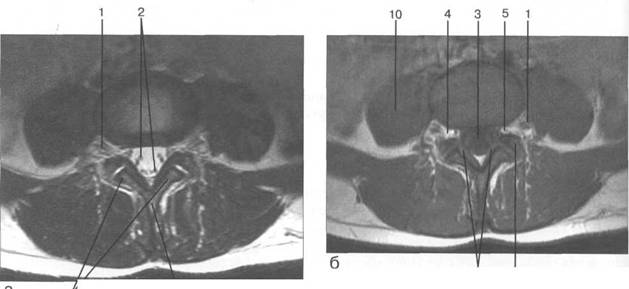

MPT. Cw_v.

Su-SIir

Паутинная мозговая оболочка состоит из к 141s183b 83;еточной мембраны, к которой прикрепляется